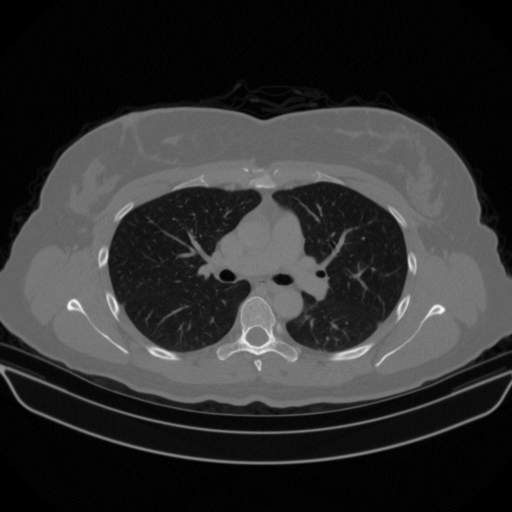

Original VENOUS CT scan

Full window (WL 1023.5, WW 4095 β†’ Low βˆ’1024, High +3071)

Lung window (WL -600, WW 1500 β†’ Low βˆ’1350, High +150)

Mediastinum window (WL 40, WW 400 β†’ Low βˆ’160, High +240)